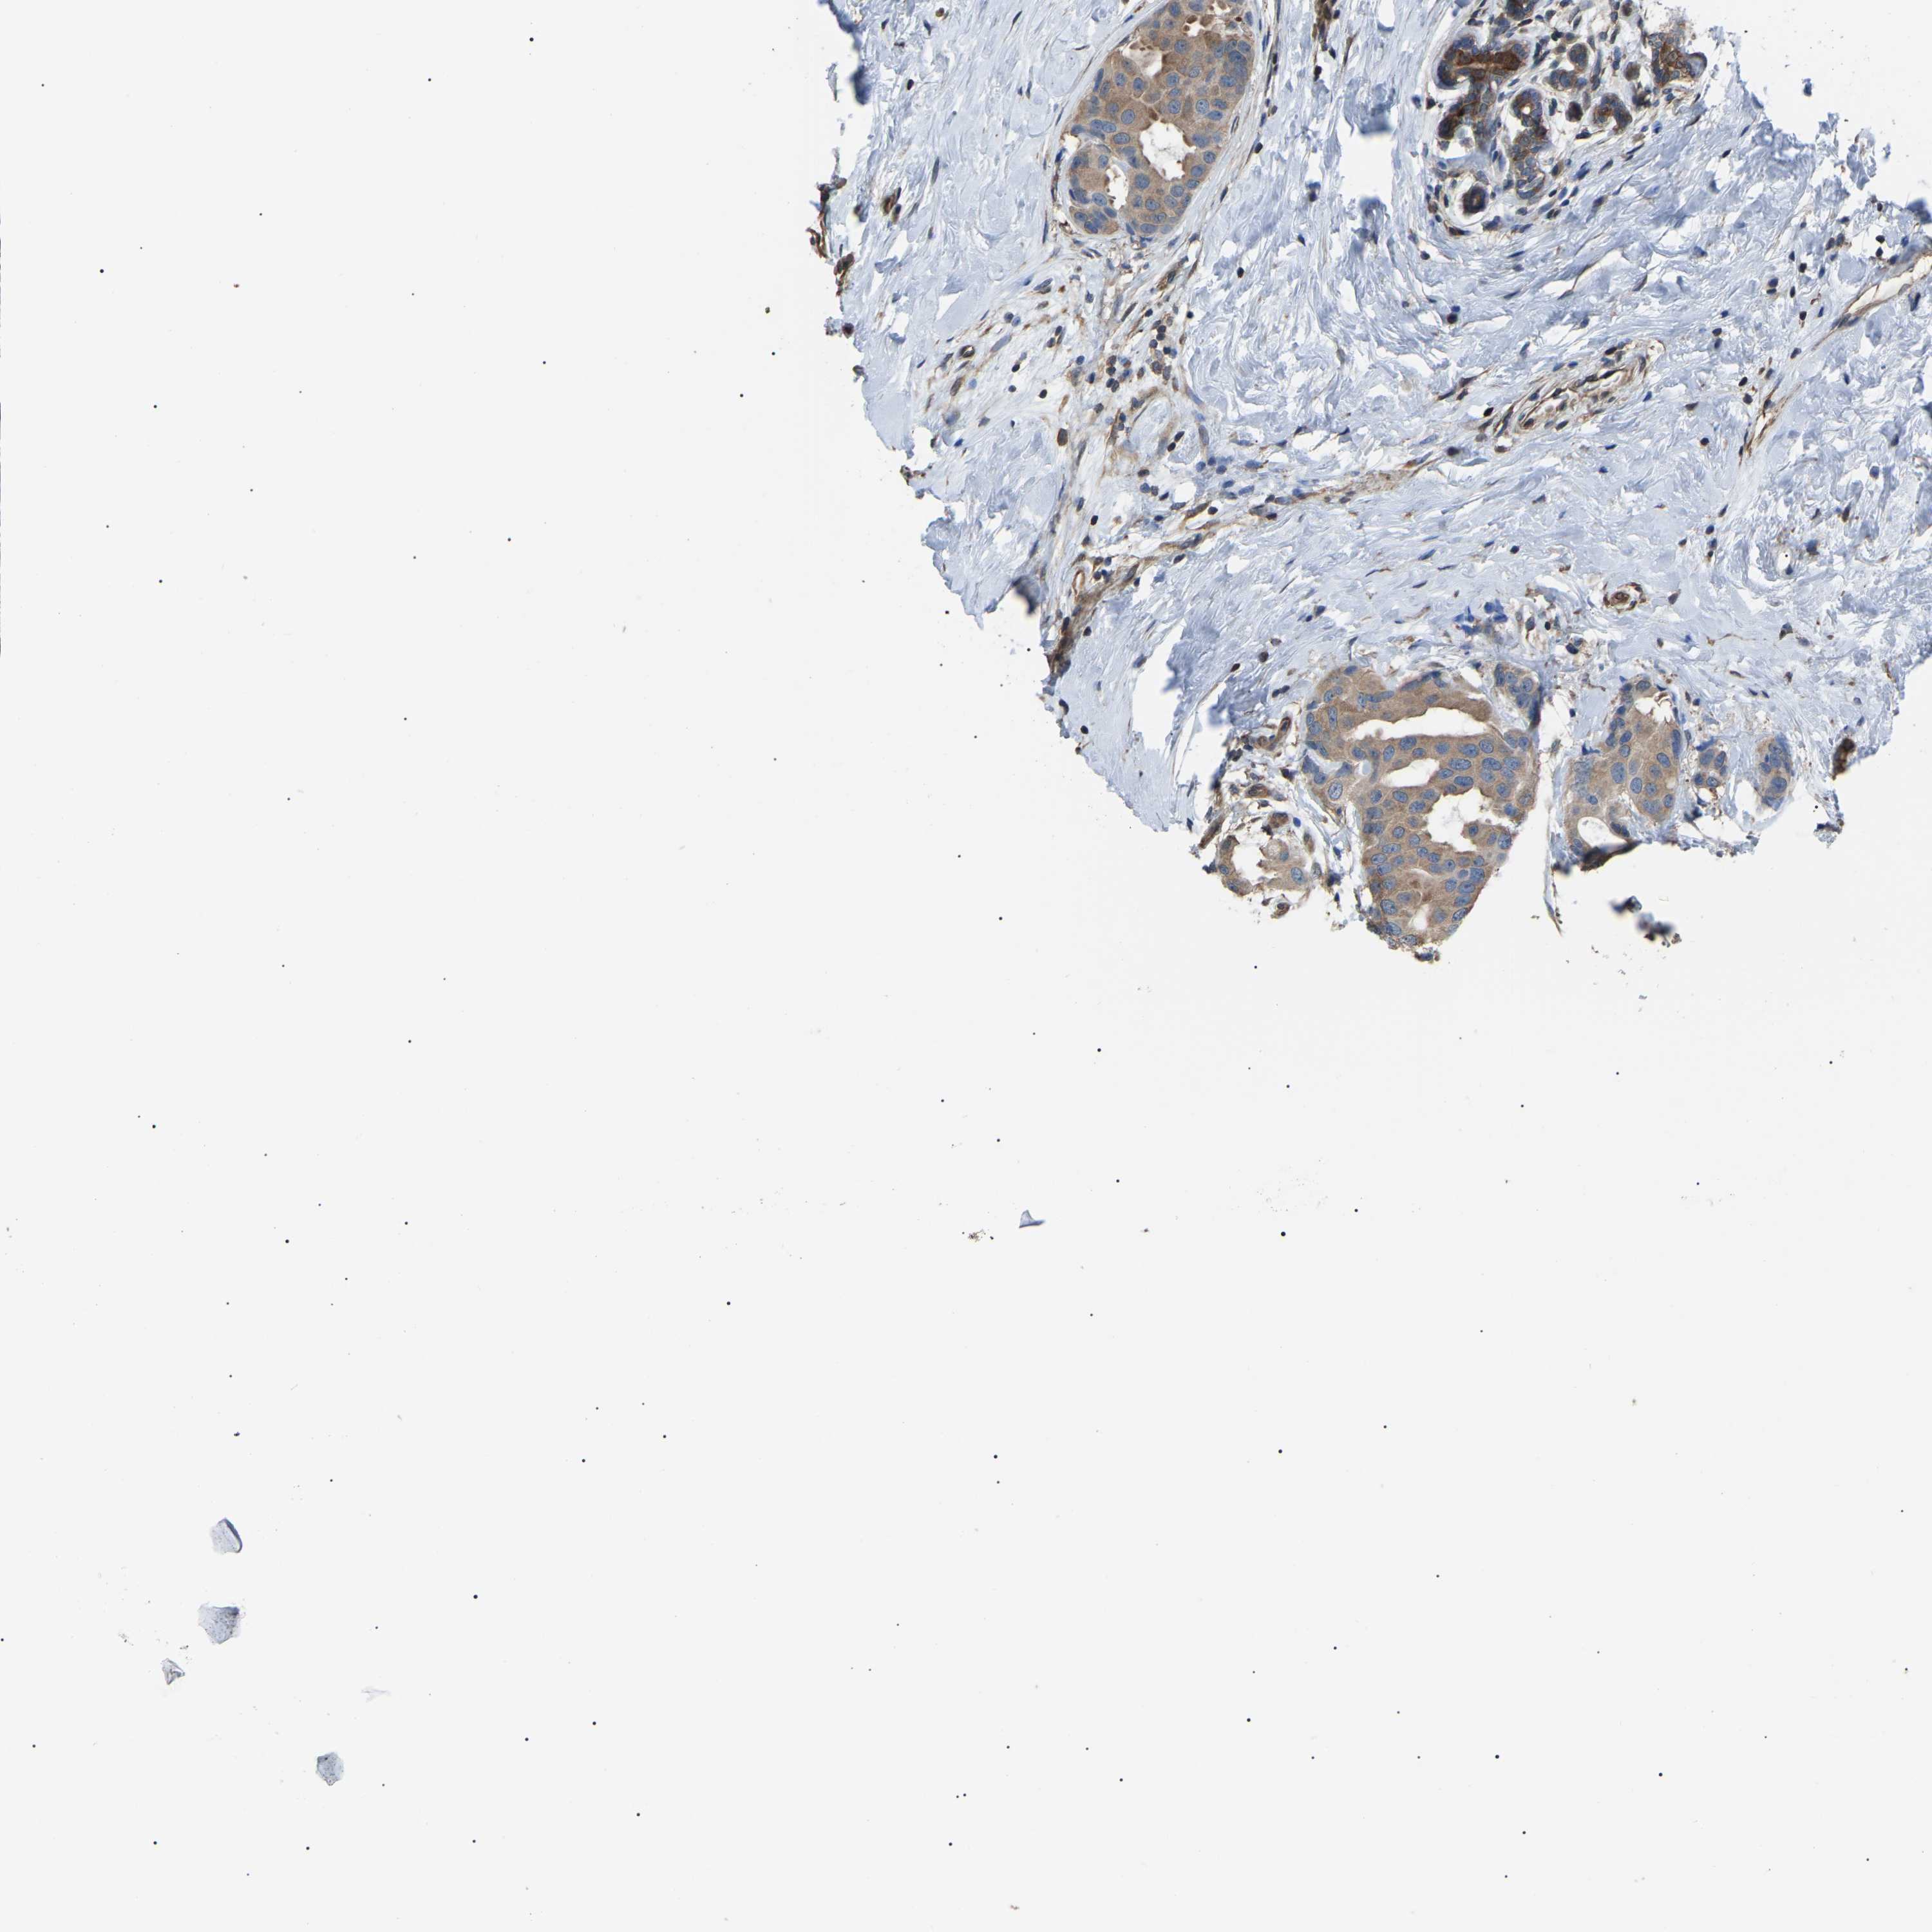

CANCER BREAST CANCER Show tissue menu

BRCA TCGA BRCA VALIDATION PROTEIN EXPRESSION

ANTIBODIES

AND

VALIDATION